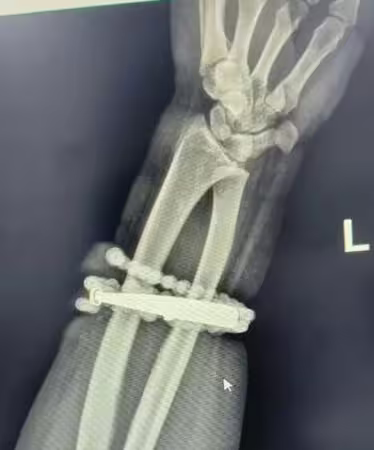

根據《巴士的報》報導,龔女長期佩戴首飾,即便體重增重、手鐲變緊也部願取下,手腕疼痛劇烈、紅腫明顯,兩週前情況更加惡化,甚至有膿液滲出,她仔細查看才驚覺,手鐲與串珠竟已「長進肉裡」,無法自行取下。

龔女她急忙就醫,醫師檢查後發現,飾品已深深嵌入皮膚與肉中,導致嚴重感染。對此,醫師解釋,這是典型的首飾長期壓迫與摩擦,加上細菌感染,造成慢性發炎與肉芽組織增生,手鐲成了刺激與污染的病灶,若再延誤治療,恐引發敗血症或手臂功能受損。